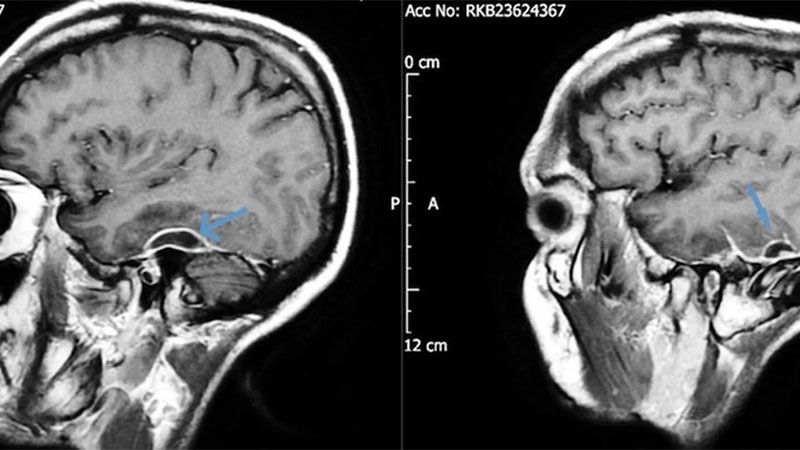

Desde el servicio de emergencias pidieron una tomografía de cabeza y encontraron en el paciente acumulaciones de pus en el tejido que rodeaba su cerebro. Los análisis de sangre revelaron que la bacteria que causó la grave infección fue la Pseudomonas aeruginosa, y se trasladó a través de un pedazo de algodón que formaba parte de un hisopo que se había desprendido dentro de la cabeza del paciente hacía años. La infección, también conocida como otitis externa necrosante, podría afectar los nervios faciales, causando secuelas similares a las de un accidente cerebrovascular. Sin embargo, en este caso y a partir del descubrimiento, se procedió a retirar el algodón con anestesia y después de ocho semanas de antibióticos intravenosos, el hombre se recuperó por completo.